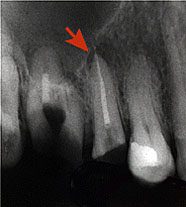

Заболевание требует неотложного вмешательства стоматолога: обеспечивают отток экссудата от верхушки корня зуба, прочищают его корневой канал. При выраженных воспалительных явлениях назначают антибиотики, электрофорез, УВЧ-терапию и др. Лечение завершают пломбированием корневых каналов. В сильно запущенных случаях зуб приходится удалять.